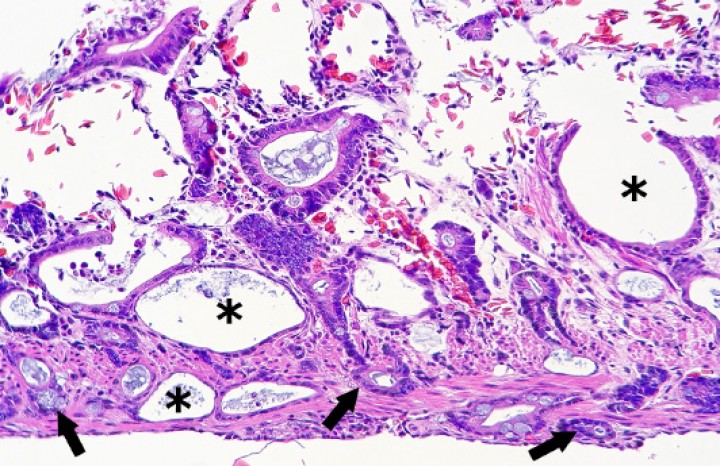

Se observaron 8 neoplasias, diagnosticadas en 6 de los 131 (4,6%) anfibios. Dos correspondían a adenocarcinomas sin evidencias de metástasis: uno intestinal en una rana dardo verdinegra (Dendrobates auratus) (Fig. 8), y otro en un tejido no identificable en un sapo buey (Rhinella schneideri); este último mostraba, además, hemangiomas en el pulmón (Fig. 9). El adenocarcinoma intestinal de la rana dardo verdinegra (Dendrobates auratus) consistía en una proliferación mal delimitada y no encapsulada de enterocitos que formaban criptas y glándulas variablemente dilatadas o, raramente, nidos diminutos compactos que invadían de forma amplia todas las capas del segmento intestinal afectado (Fig. 8) y mostraban anisocitosis, anisocariosis, pleomorfismo y anaplasia bajos a moderados, sin actividad mitótica aparente. Otros 3 anfibios padecieron neoplasias hematopoyéticas: un linfoma multicéntrico con componente epiteliotrópico en una rana tomate (Fig. 10) y dos neoplasias de células redondas no identificables de forma clara mediante la tinción rutinaria en un sapillo balear (Alytes muletensis) y un axolote (Ambystoma mexicanum). Otro sapillo balear (Alytes muletensis) mostraba una proliferación multicéntrica benigna de epitelio renal tubular (Fig. 11) organizado en estructuras tubulares, papilares y quísticas (Fig. 12), compatible con adenomatosis renal (adenomas múltiples); se observó atipia celular en escasas células neoplásicas y en células epiteliales de túbulos no neoplásicos. Adicionalmente, en este sapillo balear (Alytes muletensis) se apreció un foco hepático bien delimitado y no encapsulado de proliferación de hepatocitos compatible con hiperplasia nodular o un hepatoma; la ausencia de tríadas portales dentro de esta neoplasia es compatible con un hepatoma (Fig. 13).

<p>Intestino delgado; rana dardo verdinegra (<em>Dendrobates auratus</em>). Proliferación neoplásica de epitelio entérico, que invade todas las capas (flechas) y forma estructuras glandulares variablemente dilatadas (asteriscos). Hematoxilina-eosina, x240.</p>

Intestino delgado; rana dardo verdinegra (Dendrobates auratus). Proliferación neoplásica de epitelio entérico, que invade todas las capas (flechas) y forma estructuras glandulares variablemente dilatadas (asteriscos). Hematoxilina-eosina, x240.